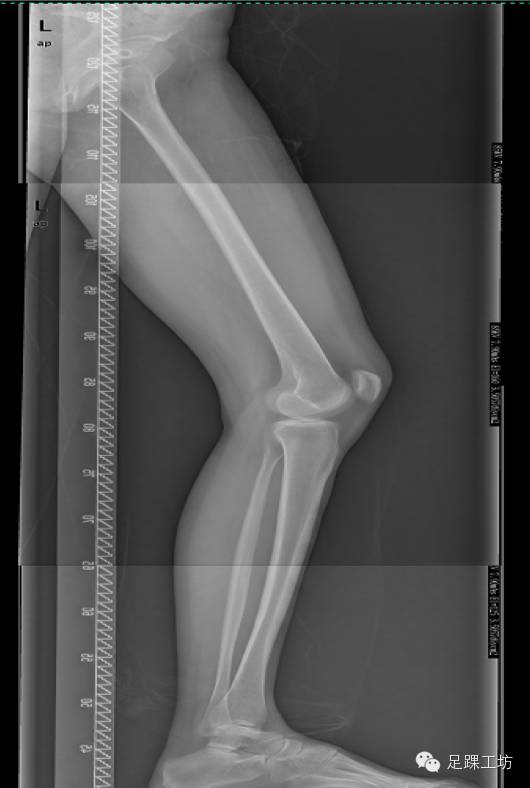

X线

后辗转至广州某三甲医院进行了全面影像学检查